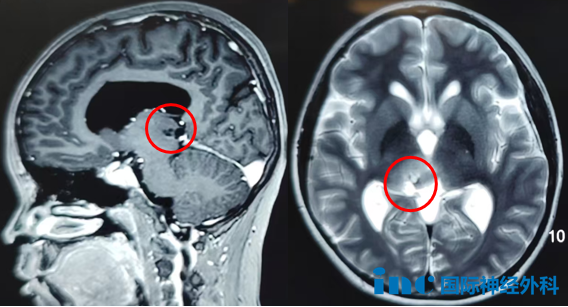

手术难点:位置深,MRI显示左侧丘脑占位性病变,弥漫性生长、侵入脑实质。

手术风险:丘脑海绵状血管瘤非常罕见,出血后往往引起偏瘫等神经功能障碍,临床上治疗非常棘手。形象地比喻一下,丘脑就像插头转换器,再多的数据线,如果没有这个转换器,也不能把信息输送到大脑。所以一旦丘脑损伤,患者可能变成“木头人”,即对外界的刺激没有反应。对于法学专业的小雨来说,这简直晴天霹雳。